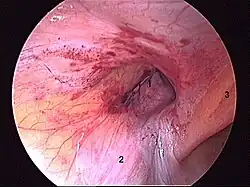

Ryc. 3 Śródoperacyjny obraz przepukliny pachwinowej nawrotowej. 1. mnogie ubytki w powięzi poprzecznej.

Przepuklina pachwinowa nawrotowa jest to przepuklina, która wystąpiła ponownie po uprzednio wykonanym zabiegu operacyjnym przepukliny (Ryc. 3).

Herniorafia polega na anatomicznej rekonstrukcji warstw powłok jamy brzusznej w okolicy przepukliny. Przeprowadza się ją po wypreparowaniu worka przepuklinowego i repozycji (cofnięciu) zawartości worka do jamy brzusznej. Pierwszą tego typu operacją była wykonana w roku 1889 operacja metodą Bassiniego[5]. Następne lata przyniosły przeszło 150 modyfikacji tej metody, z których najbardziej popularną stała się metoda Shouldice’a. Wszystkie techniki bazujące na zasadzie herniorafii doprowadzają, szczególnie w przypadku dużych przepuklin do napięcia w okolicy pachwinowej z następowym zaburzeniem anatomii tej okolicy[2][6]. Dodatkowo przy dużym napięciu tkanek dochodzi do ich przecinania przez założone szwy, co prowadzi do wznów pooperacyjnych. (Ryc. 3)